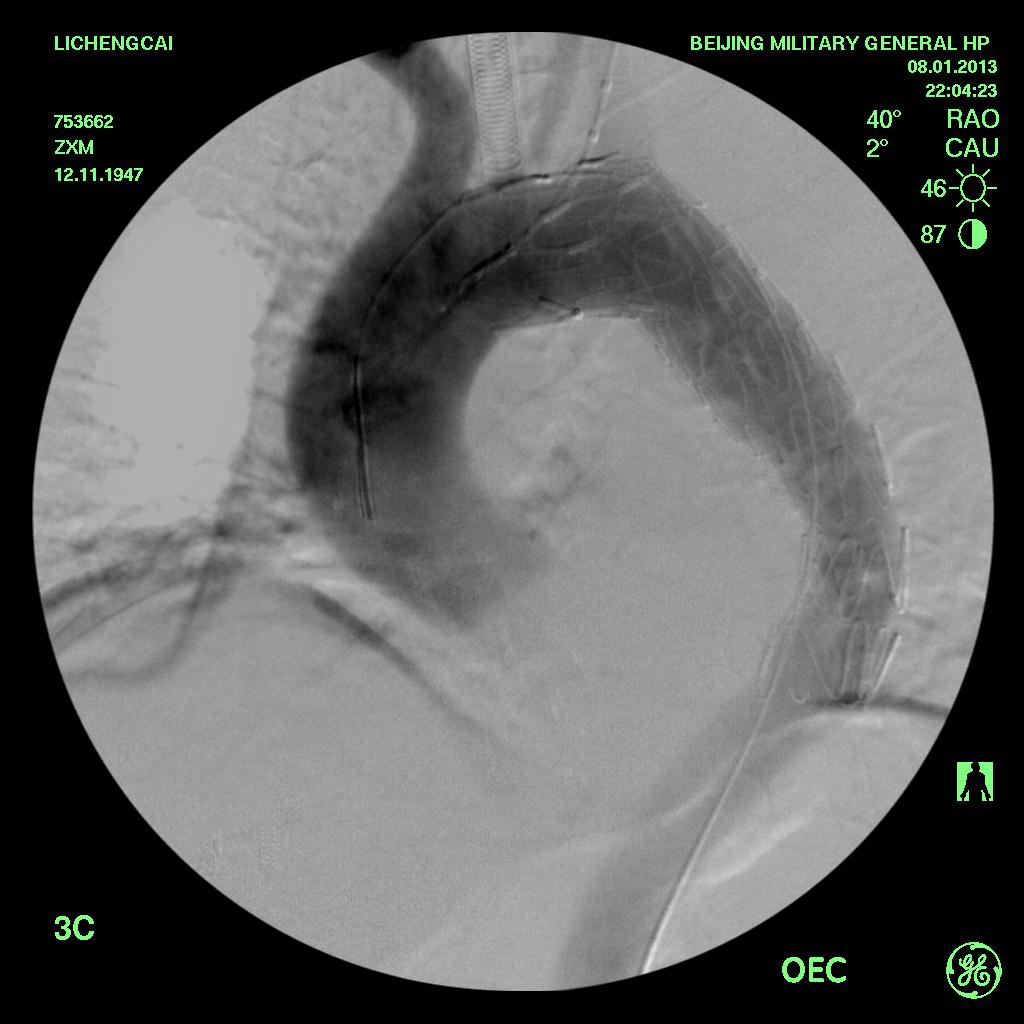

确诊主动脉夹层的主要辅助检查手段是:CT血管造影(CTA),磁共振检查(MRA)或是直接的数字剪影血管造影(DSA)。

左图为治疗前,右图植入支架后